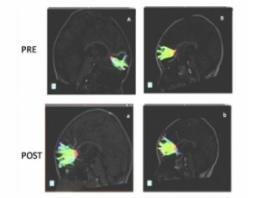

L'équipe a suivi 23 enfants en bonne santé entre les âges de 5 et 6 ans. Tous les enfants étaient droitiers et n'avaient aucun antécédent de troubles sensoriels, perceptifs ou neurologiques. Aucun des enfants n'avait été formé à aucune discipline artistique dans le passé. Les jeunes participants ont passé une évaluation cérébrale par IRM du tenseur de diffusion, une technique qui permet d'identifier de micro changements de structure dans la substance blanche du cerveau.

La substance blanche, champ de connectivité : la substance blanche du cerveau est composée de millions de fibres nerveuses appelées axones qui agissent comme des câbles de communication reliant différentes zones du cerveau. L'imagerie du diffuseur de tension produit une mesure, appelée anisotropie fractionnaire (FA), du mouvement des molécules d'eau extracellulaires le long des axones. Dans la substance blanche en bonne santé, la direction des molécules d'eau extracellulaires est assez uniforme et les mesures en anisotropie fractionnée relativement élevées. Lorsque le mouvement de l'eau est plus aléatoire, les valeurs de FA diminuent, ce qui suggère des anomalies.

Ø L'étude montre que 9 mois de formation musicale sont associés à une augmentation de la mesure en FA et une augmentation des axones dans différentes zones du cerveau, dont le cortex frontal.